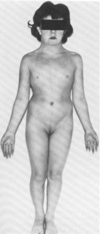

ALTURA : 1.51 SEM DESENVOLVIMENTO SEXUAL. HIPOGONADISMO HIPERGONADOTROFICO. AS ALTERAÇÕES RESPONSÁVEIS : AMNORRÉIA PRIMÁRIA - AUSÊNCA DE MENSTRUAL AOS 14 ANOS ASSOCIADA Á FALHA NO DESENVOLVIMENTO. APRESENTA INFERILIDADE PRIMARIA --\> APÓS 1 ANO NÃO ENGRAVIDOU. FSH ESTÁ ELEVADO , SUGERINDO PROBLEMA NO OVÁRIO ( ELE NÃO TÁ FUNCIONANDO --\> PROBLEMA NO COMPARTIMENTO 2) --\> AUSNECIA DE OVULAÇÃO. PACIENTE COM SINDROME DE TURRNER....